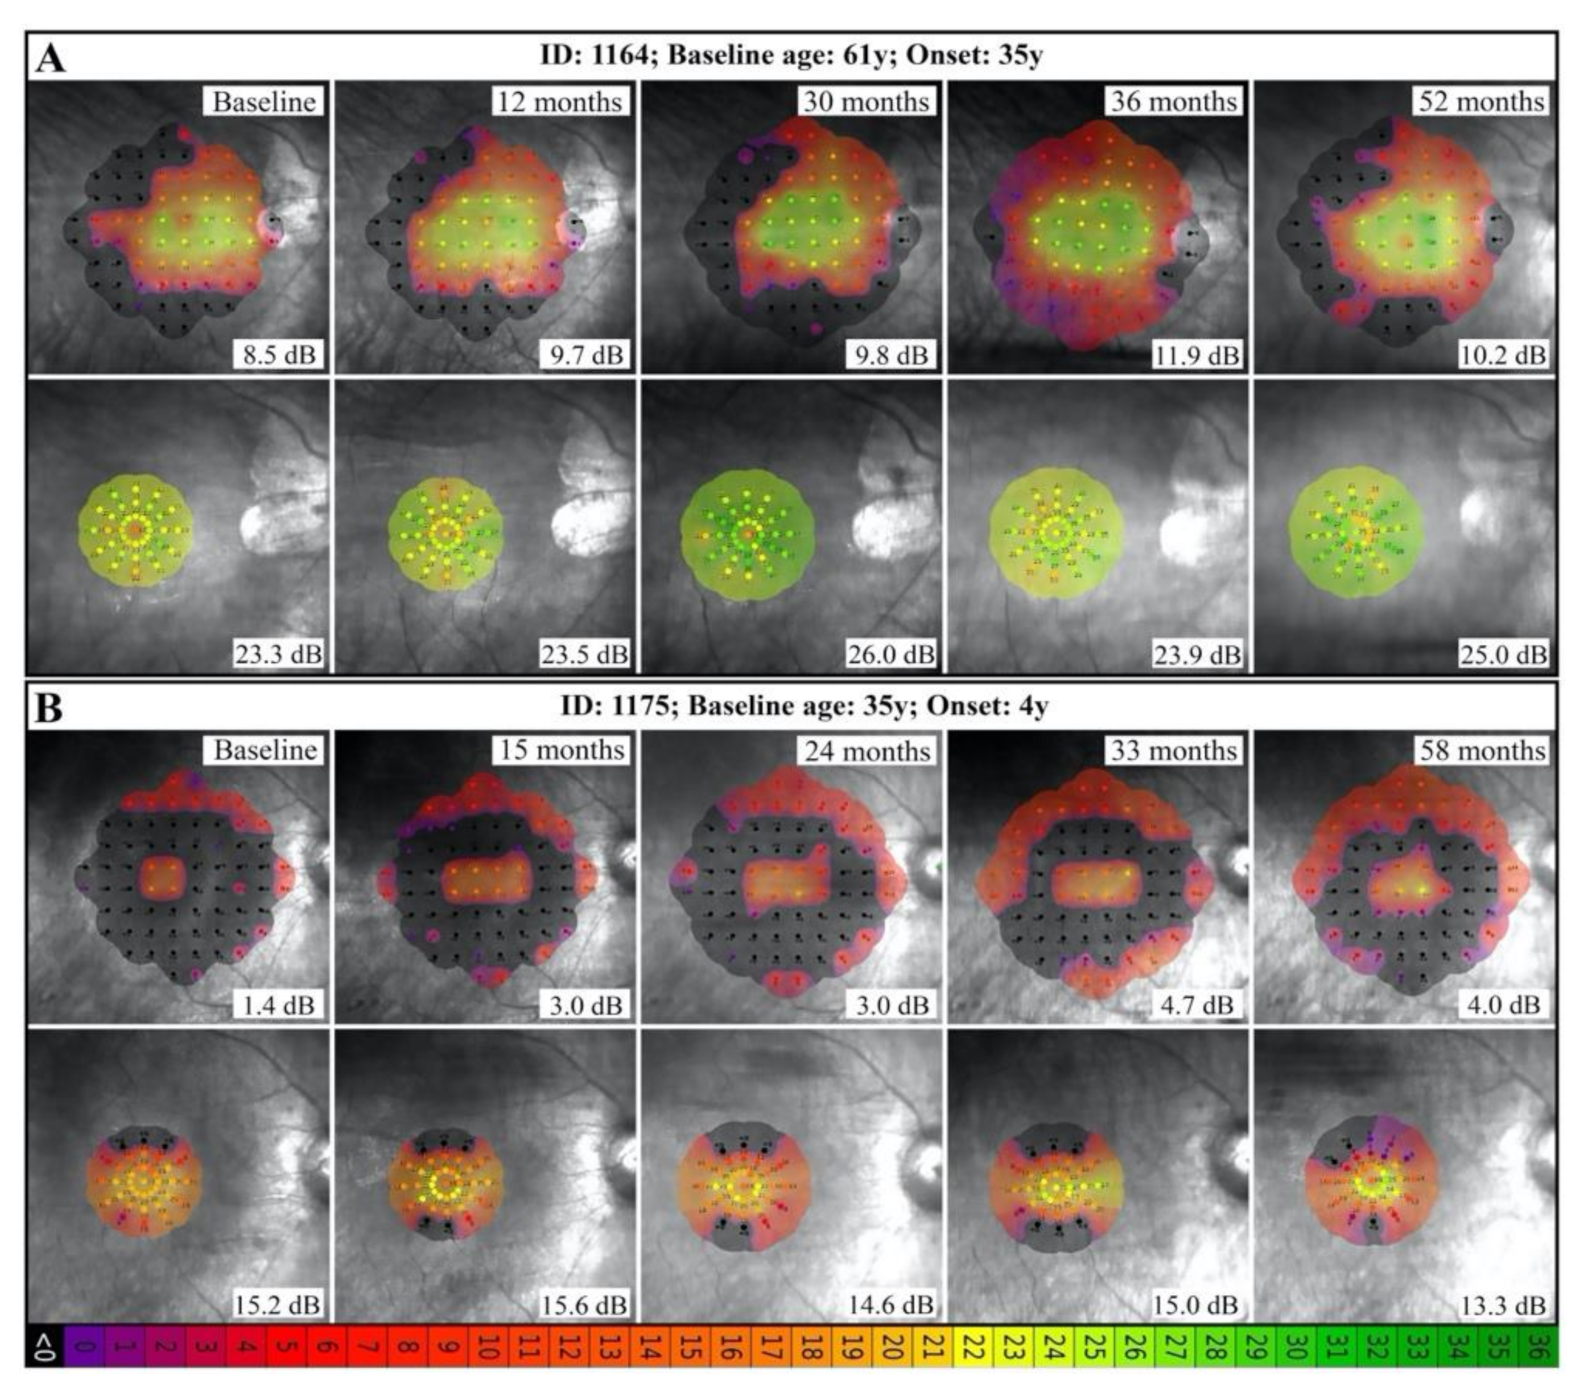

3.3. Natural History of Disease Progression

3.4. Phenotype Patterns

4.2. RP11 Progression May Not Follow a First-Order Exponential Curve